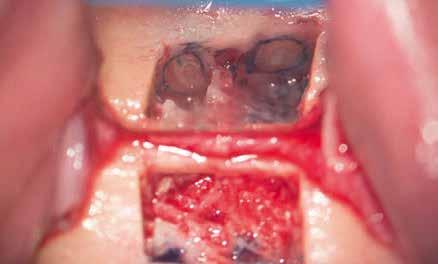

A preprotetikai fázisban el kell látnunk a diagnosztizálásra került kórfolyamatokat, megfelelő pozícióba kell állítanunk a megtartani kívánt fogakat, pótolnunk kell az elvesztett csontállományt, valamint gondoskodnunk kell az íny megfelelő állapotáról. Ha szükség van rá, úgy a foghiányok pótlására szolgáló dentális implantátumok is ebben a fázisban kerülnek behelyezésre. Általánosságban elmondható, hogy azokat a kezeléseket, amelyek befejezése biológiai okok miatt hosszú időt vesz igénybe (pl.: fogszabályozás, csontpótlás, implantáció), a lehető leghamarabb érdemes elkezdeni.